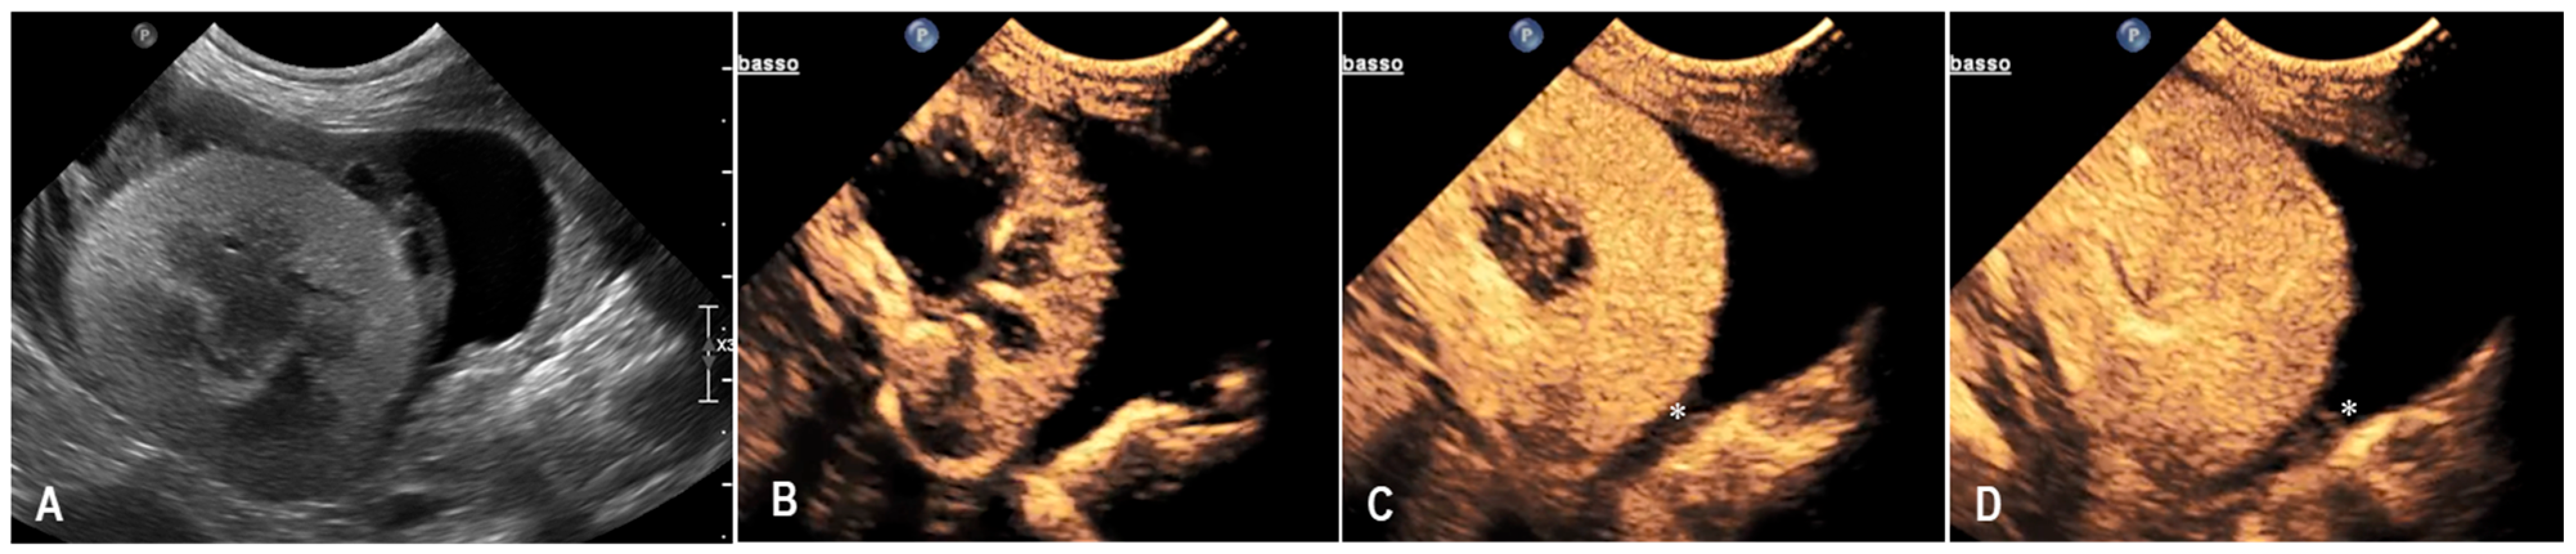

3.1. Case 1